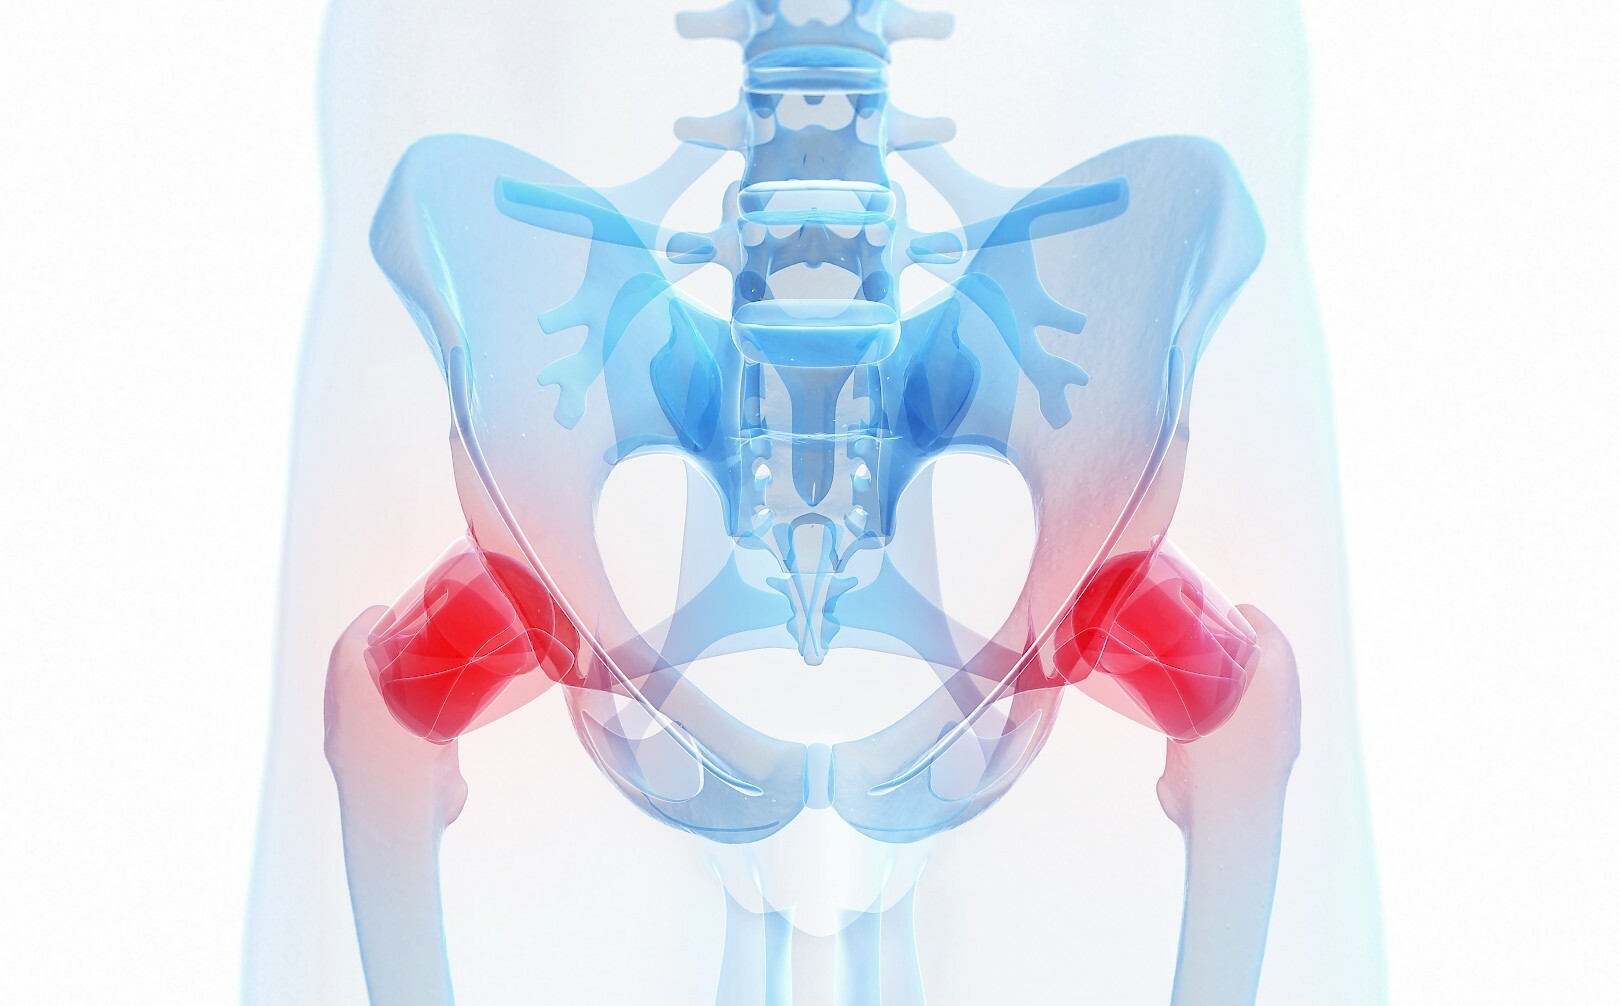

Боль в малом тазу у женщин: Причины и подходы к лечению